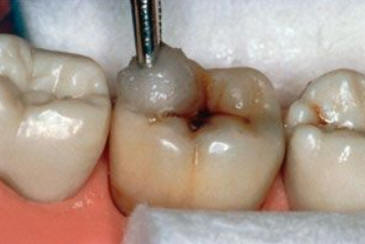

El examen visual debe emprenderse con los dientes completamente secos y con una buena iluminación.  El uso de amplificación de imagen también puede ayudar en el diagnóstico. El uso de una sonda se restringe al levantamiento de placa y detritos de comida.

El diente al lavarse y secarse con la jeringa triple deja expuesto esmalte blanquecino escarchado o opaco que delata un proceso de desmineralización, debido a que el agua se evapora de los microporos. Ver círculos rojos

Una mancha oscura de dentina que se observa a través del esmalte intacto,  adyacente a la fosa y reborde marginal,  indica la presencia de desmineralización. (Imagen 0229)

Las Radiografías Bite-Wing son un pre-requisito cuando se considera una restauración con sellador. Éstos no deben mostrar evidencia de caries interproximal que pueden indicar que una restauración deba ser  más extensa. Debe ser considerado que el tamaño real de la lesión es normalmente más grande que la imagen radiográfica. La Transiluminación  también puede ser un beneficio para el diagnóstico de caries oclusal y caries interproximal.